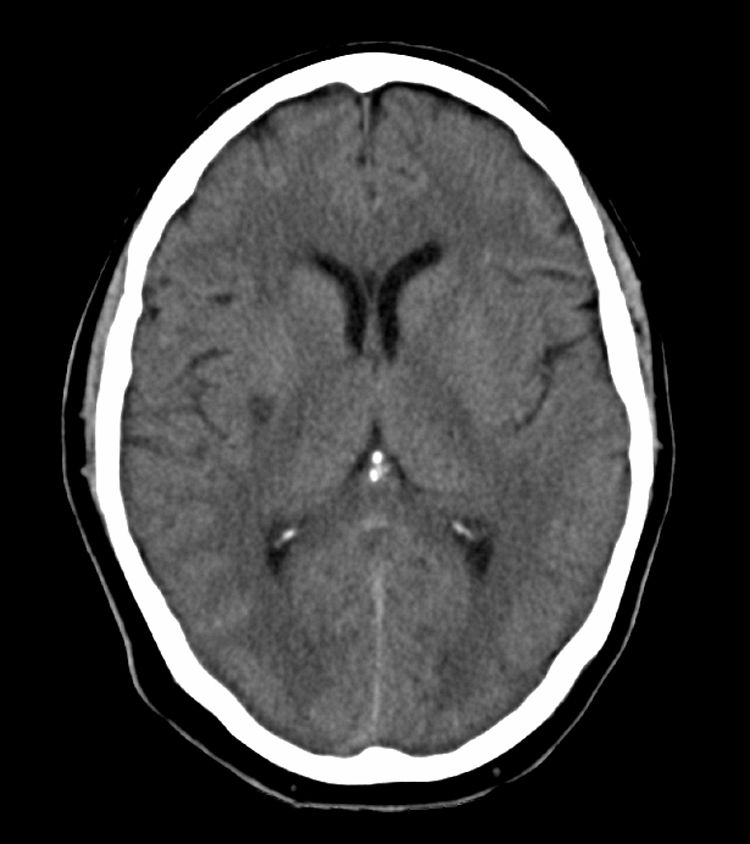

A complementary study (electrocardiogram, echocardiogram, and transcranial and supra-aortic trunk neurosonology) showed no significant changes. The routine CT scan performed 24hours after the IVT revealed an ischaemic lesion affecting the posterior third of the right putamen (Fig. 2). Eight days after admission, the patient was discharged from hospital with left hemiparesis, facial paresis, and dysarthria (NIHSS=8, modified Rankin scale=3).